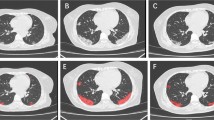

This study included 131 patients who were infected with the Delta variant of COVID-19. After screening, 106 patients with 458 follow-up CT scans were retrospectively selected and divided into complete and incomplete vaccination groups (66 and 40 patients, respectively). Imaging features were automatically extracted, and infection distribution in lung fields and progression pattern tendency were investigated. Furthermore, we extracted the most related clinical and imaging features to establish a vaccination status classification model. An independent testing dataset with 55 patients from another inpatient ward was enrolled to evaluate the generalizability of the model.

The severity of infection in the lung and lung fields of the complete vaccination group was overall lower than those of the incomplete vaccination group. A relatively earlier peak CT abnormality was found on days 8–11 in the complete vaccination group than in the incomplete vaccination group on days 12–15 after the first positive PCR time. The vaccination status classification model achieved the highest performance with an AUC of 0.929 and accuracy of 0.864 in the testing set and an AUC of 0.858 and accuracy of 0.727 in the independent testing set.

In summary, compared to the incomplete vaccination group, the fully vaccinated patients had milder CT abnormalities and earlier peak time for chest impairment. Therefore, the vaccination status is determinable through dynamic imaging and clinical features.